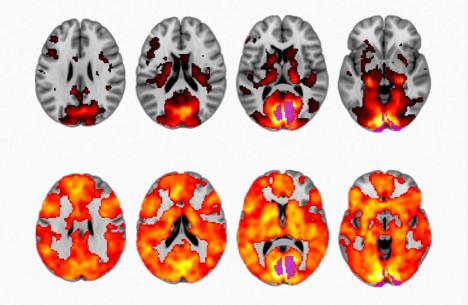

Pošto je danas moguće meriti preciznu moždanu aktivnost, naučnici su uspeli da izmere neuobičajeni krvni pritisak, aktiviranje nervnog sistema, moždanih talasa i premrežavanja subjekata pod dejstvom i došli su do neverovatnog otkrića.

Evo kako LSD utiče na mozak korisnika: